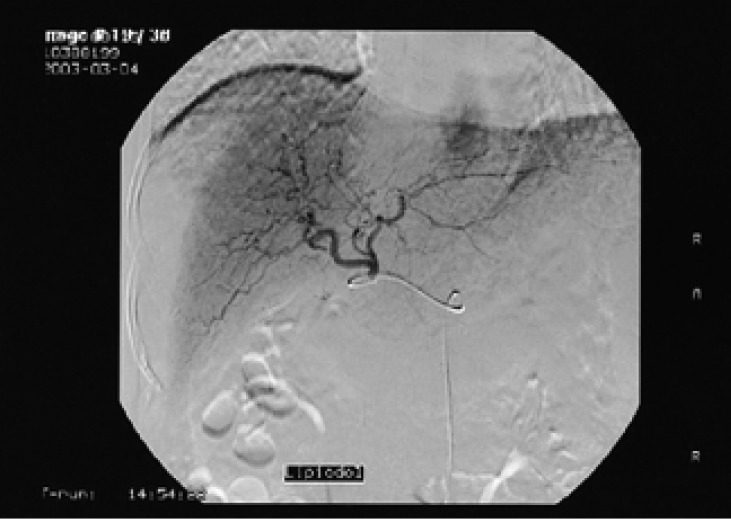

Figure 2

Hepatic angiography of the liver shows no definite tumor staining in the liver parenchyme. Lipiodol test injection was performed (Case 1).

A 59-year-old male with confirmed hepatitis C-related liver cirrhosis of over 10 years duration was admitted to our hospital in March 2003 for an evaluation of his functional and histopathologic status of the liver, and his levels of aminotransferases and alpha-Fetoprotein (AFP) that were checked at the outpatient department had persistently risen. At the time of the admission, he presented with general weakness and loss of appetite, and the vital signs were normal. The initial serology revealed mild hyperbilirubinemia with a total bilirubin of 1.3 mg/dL. The aminotransferase levels were 116 IU/L and 33 IU/L for aspartate (AST) and alanine (ALT) aminotransferase, respectively, with an alkaline phosphatase (ALP) 233 IU/L and γ-glutamyl transpeptidase (GGT) 109 IU/L. The AFP level checked on the admission was 4,720 ng/mL. The HBsAg and anti-HBs tests were negative and nonreactive. The anti-HCV (IgG) was reactive with a titer of 181.14 S/CO and the HCV (PCR) was 4+. A quantitative measurement of HCV-RNA was not carried out. The other serologic findings were normal. He was a type II diabetic and had no history of variceal bleeding, ascites, encephalopathy or any intake of herbs or alcohol before the admission. He had been followed up at the Department of Gastroenterology of the hospital since May 2002, and the aminotransferase levels checked since then were shown to be gradually increasing, and the AFP levels had increased markedly at the time of her admission (Table 1). As shown in the Table 1, the aminotransferases (AST/ALT) and AFP levels had increased from 57/18 IU/L and 18.1 ng/mL, respectively, in May 2002 to 196/71 IU/L and 4,720 ng/mL, respectively, in February 2003 until the commencement of antiviral therapy. Computed tomography (CT) of the liver taken during the admission showed no definite mass or intrahepatic focal lesion in the liver (Figure 1A). There were no other clinically significant abnormalities found on the CT scan. Hepatic angiography was carried out for the markedly elevated AFP level to rule out any possibility of hepatocellular carcinoma, but no definite tumor staining was noted in liver parenchyme (Figure 2). The sequentially performed liver biopsy showed severe porto-periportal inflammatory activity, mild lobular inflammatory activity and septal fibrosis, and these findings were compatible with chronic active hepatitis in liver cirrhosis (Figure 3). The post-lipiodol hepatic CT scan taken 2 weeks after the angiography for detecting any hidden tumor also showed no focal lesion or remnant of lipiodol staining in the liver (Figure 1B).The patient was treated with antiviral therapy of Interferon (IFN) 3 million units three times a week along with Ribavirin 500 mg twice a day, and then the patient was discharged. The aminotransferases (AST/ALT) and AFP levels taken on follow up at the outpatient department after discharge decreased to 89/90 IU/L and 40.6 ng/mL, respectively, over a period of 3 months. He has taken the anti-viral therapy (IFN and Ribavirin) for over 6 months, and the aminotransferase levels have not changed significantly, and the AFP level did not increase any further. Moreover, the HCV (PCR) that was checked at the end of the antiviral therapy had converted to 'negative'. During the course of the therapy, follow-up imaging studies, abdominal ultrasonography and liver CT scan were undertaken along with serologic evaluation, and yet no evidence of tumor in the liver parenchyme was discovered.- Case 2